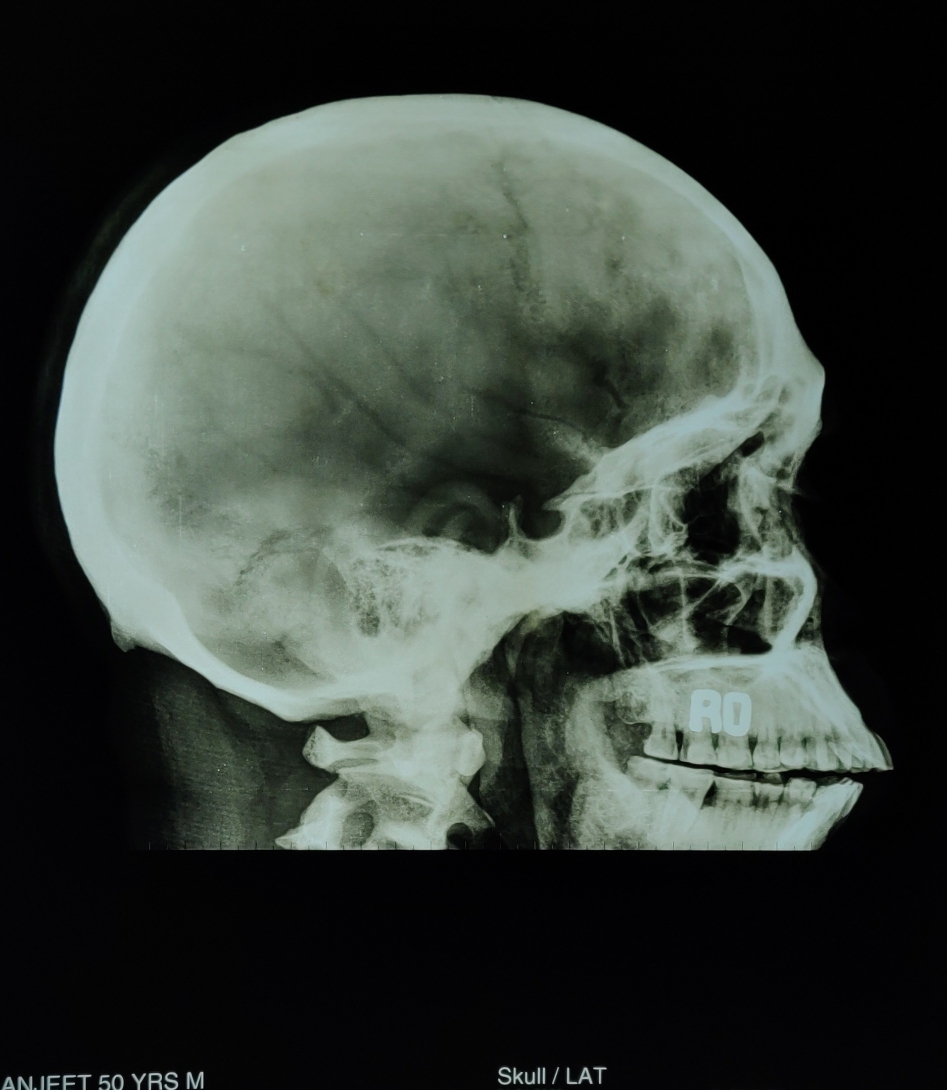

Define Marble Bone Disease . osteopetrosis is group of a rare disorders that cause bones to grow abnormally and become overly dense. Therefore, the disease is often. osteopetrosis, or marble bone disease, is a rare skeletal disorder due to. osteopetrosis is a congenital metabolic bone disease caused by defective osteoclastic resorption of immature bone that presents with. osteopetrosis is marked by increased bone density due to a defect in bone reabsorption by cells called. ‘osteo’ means bone, and ‘petrosis,’ meaning stone.

(PDF) Osteopetrosis (Marble Bone Disease) A Rare Disease in Children

Figure 3 from Osteopetrosis (Marble Bone Disease) A Rare Disease in Define Marble Bone Disease ‘osteo’ means bone, and ‘petrosis,’ meaning stone. Therefore, the disease is often. osteopetrosis is a congenital metabolic bone disease caused by defective osteoclastic resorption of immature bone that presents with. osteopetrosis, or marble bone disease, is a rare skeletal disorder due to. osteopetrosis is marked by increased bone density due to a defect in bone reabsorption. Define Marble Bone Disease.